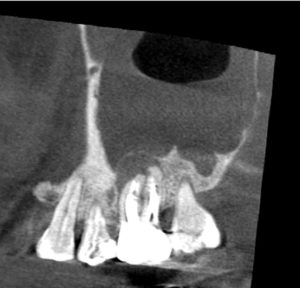

この後歯茎を開いて、はみ出したMTAセメントと除去しきれていない外部吸収部を除去して、グラスアイオノマーというセメントにより同部を埋めました(赤矢印)。

これも言葉にして書くと簡単なのですが、これをピッタリ埋めるのが非常に難しかったです。

珍しい症例なので、頻繁に出会うことはないと思います。

この病気は適切な方法を取らなければ治すことができませんし、正直、最も難しい治療の一つでした。